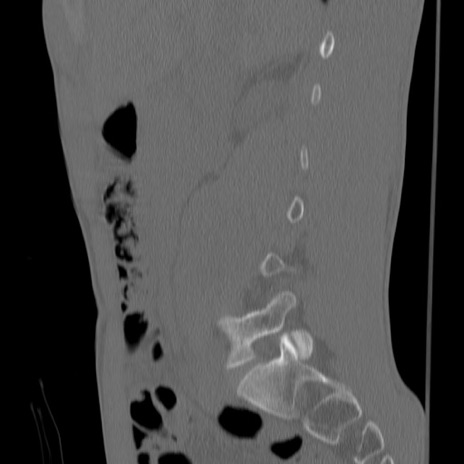

症例3 腰椎CT(矢状断像)

【症例】30歳代男性

【主訴】腰痛

【現病歴】本日旅行先で観光中に、友人と衝突し転倒し受傷。

【身体所見】麻痺なし、右下腿内側前面外側、左下腿内側に知覚鈍麻・しびれ

異常所見と診断は?

腰椎CT